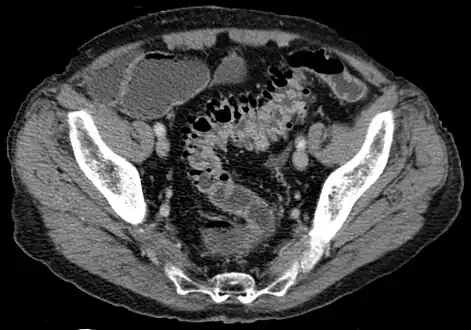

- Contrast CT is the investigation of choice in acute episodes of diverticulitis and where complications exist.

CT scan showing extensive diverticulosis of the sigmoid colon -